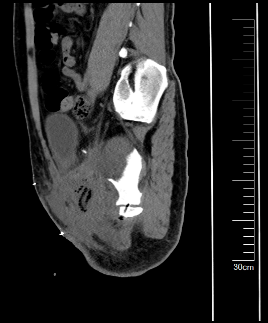

通过3D建模的精准评估,小王右耻骨软骨肉瘤体积达到了1600立方厘米(1600623.71立方毫米),肿瘤下极自右大腿中段向上,内侧贴大腿皮肤,外侧推压内收肌群及股动静脉,穿过骨盆右闭孔,紧贴右髋臼内侧壁生长,骨盆内占位部分推压膀胱。

图片 7.png

软件测算肿物体积